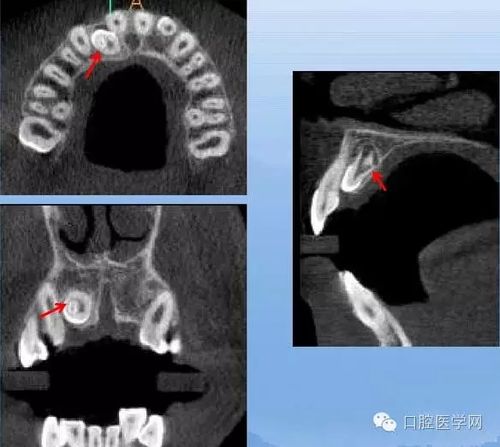

畸形舌侧窝x线表现:舌隆突特别突起,在舌面可见致密高起的小牙尖.

临床分类 畸形舌侧窝 舌侧窝呈囊状深陷,利于致龋菌滋生,同时囊底